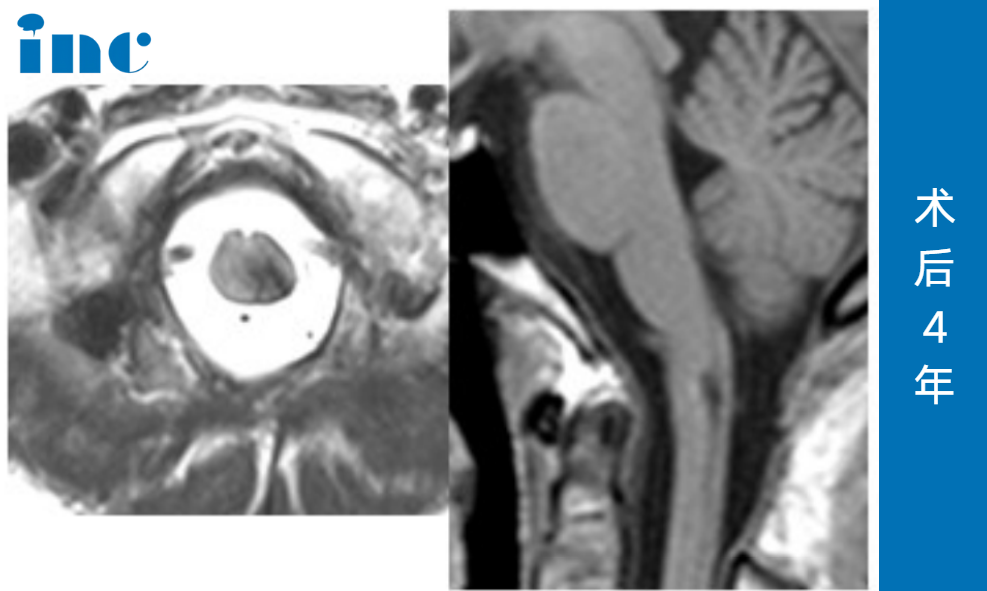

更令人振奋的是,2025年7月的最新MRI复查(见图)进一步验证了这一结果:海绵状血管瘤已经被完全切除,术区仅存手术相关的良性瘢痕及含铁血黄素沉积(均为此类术后正常表现),无任何神经功能缺损。而视频中的王女士行动自如、状态饱满。